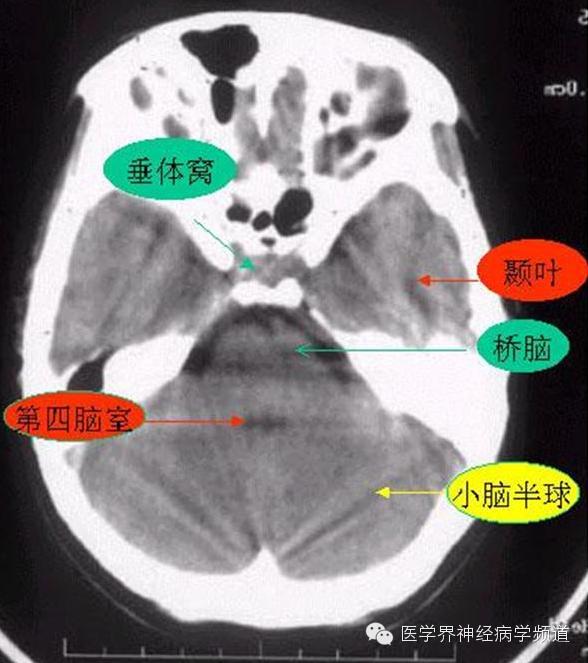

神经影像CT读片step by step